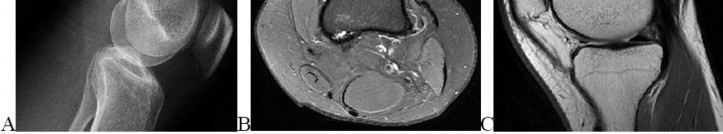

A 15-year-old male presents with deep knee pain awakening him at night. Radiographs show a permeative destructive lesion in the distal femoral metaphysis with a 'sunburst' periosteal reaction and Codman's triangle.

Biopsy confirms high-grade conventional osteosarcoma. What is the most critical prognostic factor for long-term overall survival in this patient?

Explanation

For localized high-grade osteosarcoma, the most important prognostic indicator is the histologic response to neoadjuvant chemotherapy. This is evaluated during the definitive resection. A 'good response' is typically defined as greater than 90% or 99% tumor necrosis. Patients who achieve this level of necrosis have a significantly improved disease-free and overall survival rate compared to 'poor responders' who have extensive viable tumor cells remaining.